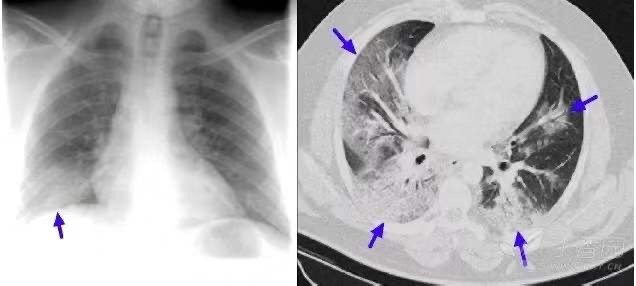

1.3 肺水肿:

患者脑出血入院,治疗后呼吸深大急促,并出现上肢与脸部水肿。

急查胸部 CT,见双肺自肺门向外弥漫基本对称的片絮状影(蓝箭),双侧胸腔后部可见液体(白箭)。

1.6. 肺渗出(浸润)性病变:浸润型肺结核

平片、CT 所见双肺散布片絮状影,并可见树芽征